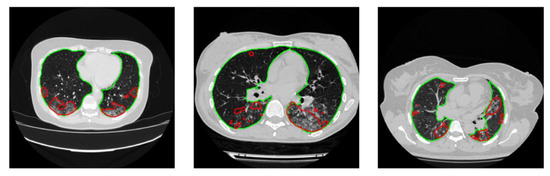

4.2. Lesion Segmentation

| Network | Accuracy (%) | IoU (%) | DSC (%) |

|---|---|---|---|

| UNet | 99.82 ± 0.18 | 90.2 ± 0.72 | 92.52 ± 0.6 |

| ResNet18 UNet | 99.82 ± 0.18 | 90.69 ± 0.72 | 92.97 ± 0.58 |

| ResNet50 UNet | 98.56 ± 0.18 | 89.09 ± 0.72 | 91.44 ± 0.58 |

| ResNet152 UNet | 99.8 ± 0.18 | 88.41 ± 0.72 | 90.80 ± 0.59 |

| DenseNet121 UNet | 99.81 ± 0.18 | 90.58 ± 0.7 | 92.88 ± 0.55 |

| DenseNet161 UNet | 99.82 ± 0.18 | 90.86 ± 0.71 | 93.07 ± 0.55 |

| DenseNet201 UNet | 99.82 ± 0.73 | 91.13 ± 0.73 | 93.36 ± 0.56 |

| ResNet18 FPN | 99.81 ± 0.2 | 91.45 ± 0.81 | 93.80 ± 0.67 |

| ResNet50 FPN | 99.81 ± 0.2 | 91.46 ± 0.82 | 93.82 ± 0.68 |

| ResNet152 FPN | 99.8 ± 0.19 | 90.66 ± 0.79 | 93.05 ± 0.65 |

| DenseNet121 FPN | 99.68 ± 0.19 | 89.09 ± 0.75 | 91.02 ± 0.6 |

| DenseNet161 FPN | 99.81 ± 0.19 | 91.11 ± 0.78 | 93.45 ± 0.64 |

| DenseNet201 FPN | 99.81 ± 0.19 | 91.85 ± 0.76 | 94.13 ± 0.62 |